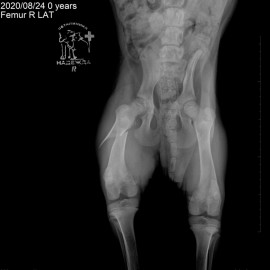

В нашу клинику обратились с жалобами на хромоту на правую заднюю лапу. После проведённых исследований был поставлен диагноз: перелом правой бедренной кости. Была проведена операция - остеосинтез правой бедренной кости.

Снимок 1 до операции